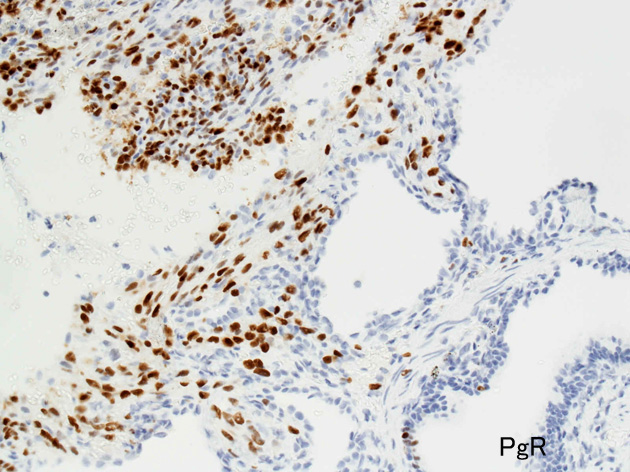

嚢胞周囲または肺血管, リンパ管, 細気管支にそうLAM cellの浸潤, 集簇を特徴とする。LAM cellには2種類が認められ, 小型紡錘形細胞と細胞質の豊富な類上皮様細胞があり, 紡錘型は主に集簇巣の中心に存在し増殖能が高い。 類上皮様LAM cellは辺縁部に多く, 増殖能は低いがHMB45を強く発現している。

LAM cellの免疫染色--SMA, desmin, vimentin(vimentinはいつも陽性とはならない)が陽性となりmuscle lineageであるが典型的な筋細胞と異なり,

免疫染色